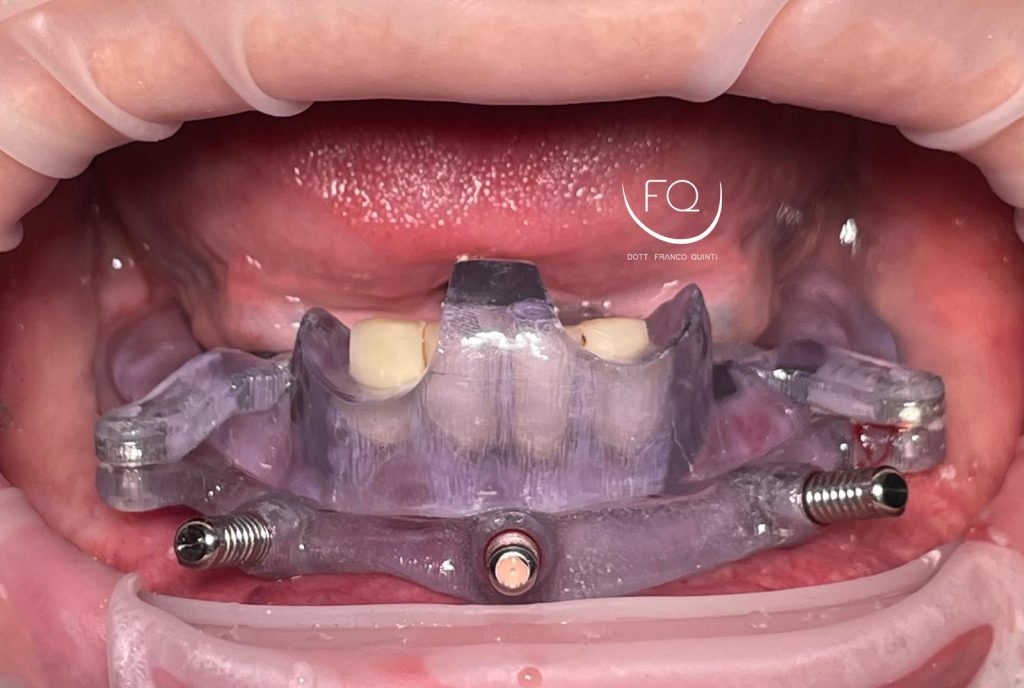

Oggi vi presento un caso di riabilitazione dell’arcata inferiore eseguito con l’utilizzo di dime scomponibili.

Il trattamento ha previsto l’inserimento di 4 impianti Prama Power di Sweden & Martina e la contestuale riabilitazione protesica provvisoria. Tra 3 mesi il caso verrà finalizzato con una protesi definitiva.